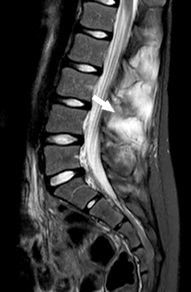

El segundo caso es una mujer de 10 años que consulta por dolor lumbar de predominio nocturno de 4 meses de evolución. No impotencia funcional para la deambulación ni otra sintomatología. A la exploración física, actitud escoliótica por dolor lumbar con leve edema a nivel de L2-L3, resto normal. Ante lumbalgia con datos de alarma (dolor nocturno), se realizan radiografía ósea (Fig. 3) y RM (Figs. 4 y 5) donde se aprecia lesión osteolítica expansiva con nivel líquido en su interior en arco posterior izquierdo de L3, así como edema de médula ósea y partes blandas y tomografía computarizada (TC; Fig. 6) donde se describe lesión lobulada y con margen esclerótico, planteando el mismo diagnóstico diferencial que en el caso anterior. Se realiza resección en bloque de la lesión y se confirma histológicamente el diagnóstico de QOA. Actualmente se encuentra sin clínica y recuperada.

| Figura 6. TC de columna vertebral: lesión osteolítica expansiva y multilobulada en lámina y pedículo vertebrales izquierdos de L3 (flecha) |